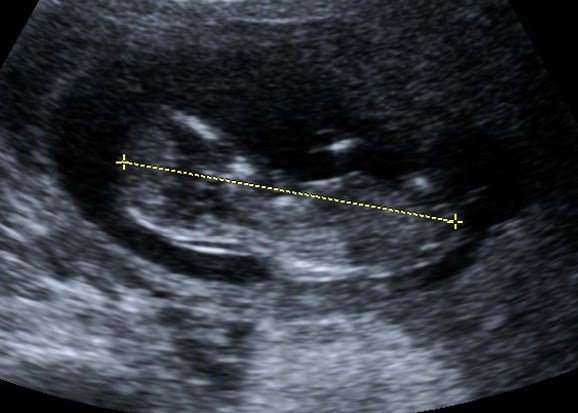

This is from my 13 week scan. I am unsure if the pictures are clear enough to take a guess at gender.

Looking forward to your guesses!

It's really hard, but my immediate thought was boy. It's slightly angled and there seems to be a line on top... If that makes sense. The bottom pic I think I see a shadow above the nub?

If that's a nub in the bottom pic I'd guess boy I think. They are a little blurry so it's hard. I think it could go either way though!

Yes I think so too if that's the nub it does seem to be angled upwards. I'm guessing boy.

Hard to say, but I definitely see an upward angle. I have to guess boy.

Maybe pink but the nub is barely seen so definitely room for error!

slightly leaning boy

at 13 weeks I would hope to see a little more going on for a boy BUT I don't feel like those pics are clear at all and I am 50-50